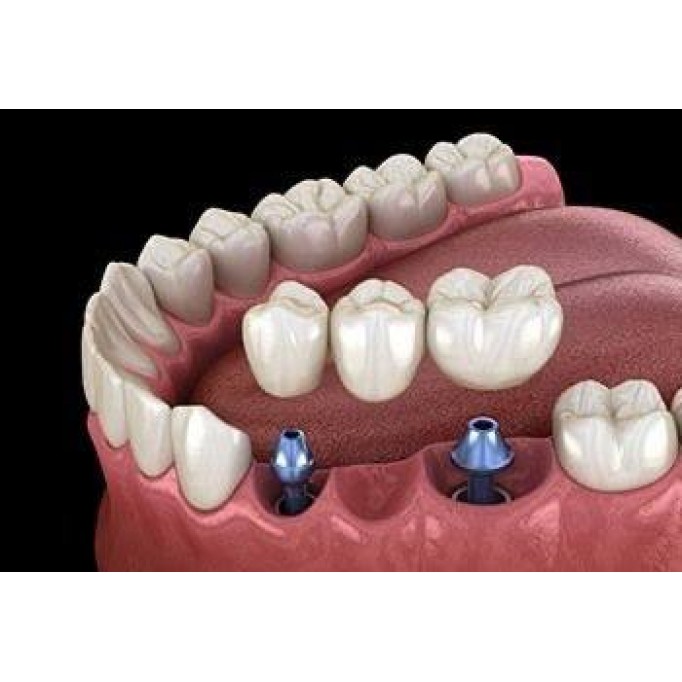

Незнімні зубні протезиНезнімні протези застосовуються в разі відсутності кількох одиниць в зубному р..

Види протезів на імплантатахІснують такі види протезів, які встановлюються на імпланти:• Коронки. За..